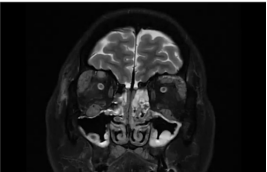

(3)眼眶增强核磁:可见右侧泪腺大于左侧,右侧内直肌明显增粗;结合既往检查,明确患者受累器官包括唾液腺、泪腺、淋巴结、鼻窦、肺、肝脏、泌尿系统、眼部等。

疗效反馈:治疗不足1个月时,患者喘息、眼睑肿胀、鼻塞流涕症状逐渐减轻至完全消失;激素减量至20mg/d时,鼻塞流涕症状轻度反复,但咳嗽胸闷未再发作;复查显示IgG4降至3.4g/L,IgE及嗜酸性粒细胞恢复正常;眼眶增强核磁提示增粗的内直肌明显缩小。